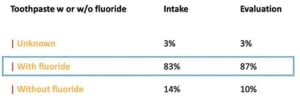

De richtlijn van de NVvP richt zich met betrekking tot stap 1 op de inventarisatie van het niveau van zelfzorg, het begeleiden en optimaliseren van mondhygiëne en gedragsverandering. Het advies is om 2x per dag te poetsen met fluoridetandpasta. Patiënten willen vaak weten wat ze moeten doen, maar doen het vaak niet omdat motivatie vaak het probleem is.